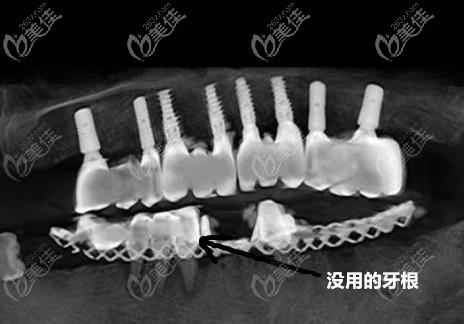

不得不說的是,這個技術比上次種牙時間節(jié)省了一大半還多,大概用了兩個多小時就種好了(其中還包括了拔除無用的牙根過程)。而且還是直接戴上了牙冠的那種。感覺只是睡了一覺的時間就好了!